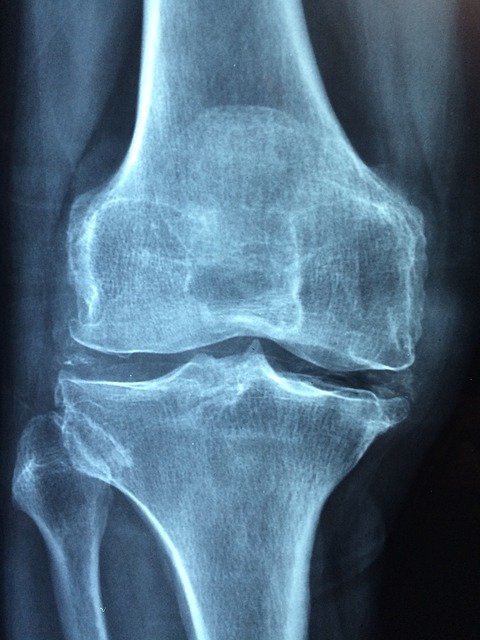

La meniscosi mediale è un processo lesivo a carico del menisco mediale, da non confondere con quello laterale. Il menisco mediale è una struttura composta da fibre e cartilagine, che dal punto di vista funzionale è d’ausilio al femore, facendo in modo che questo non subisca eccessivo carico.

La meniscosi, generalmente non è frutto di eventi traumatici o sport praticato in maniera eccessiva o sbagliata. Bensì è una condizione legata all’età (artrosi) avanzata e sovrappeso. La diagnosi avviene tramite risonanza magnetica ma spesso e volentieri, questa viene prescritta proprio perché il medico riesce a cogliere i numerosi segnali sintomatici che il paziente riferisce, unito a campanelli d’allarme come la senilità o un peso corporeo eccessivo.